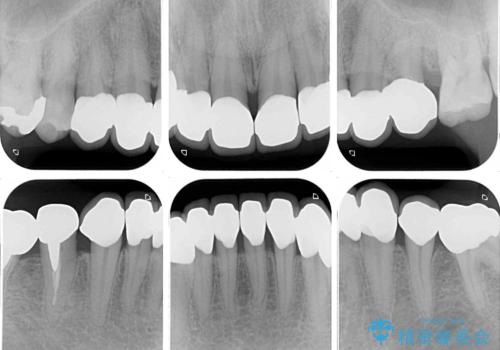

- 薬剤の影響で黄ばんでしまった前歯を気にして来院された患者様です。

お子様が大学を卒業され、経済的に余裕ができたとのことで、長年気にしていた前歯を綺麗にする決断をされたとのことでした。

奥歯の銀歯も気にはなるものの、口を開けたときに目立たないとのことで、上下ともに前歯を中心にオールセラミッククラウンにて補綴治療を行うこととしました。

咬合力が非常に強いため、就寝時には上下ともにマウスピースを使用していただくよう指導をしています。